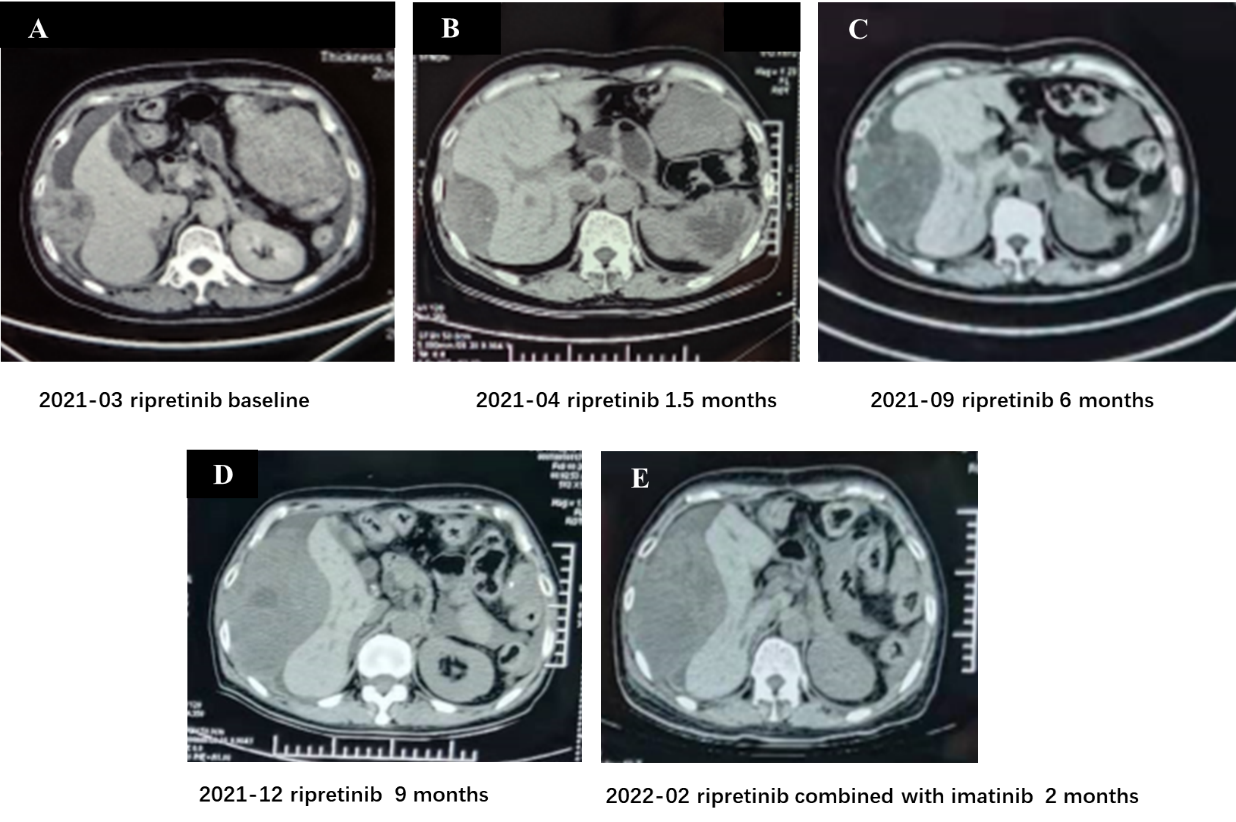

.png)